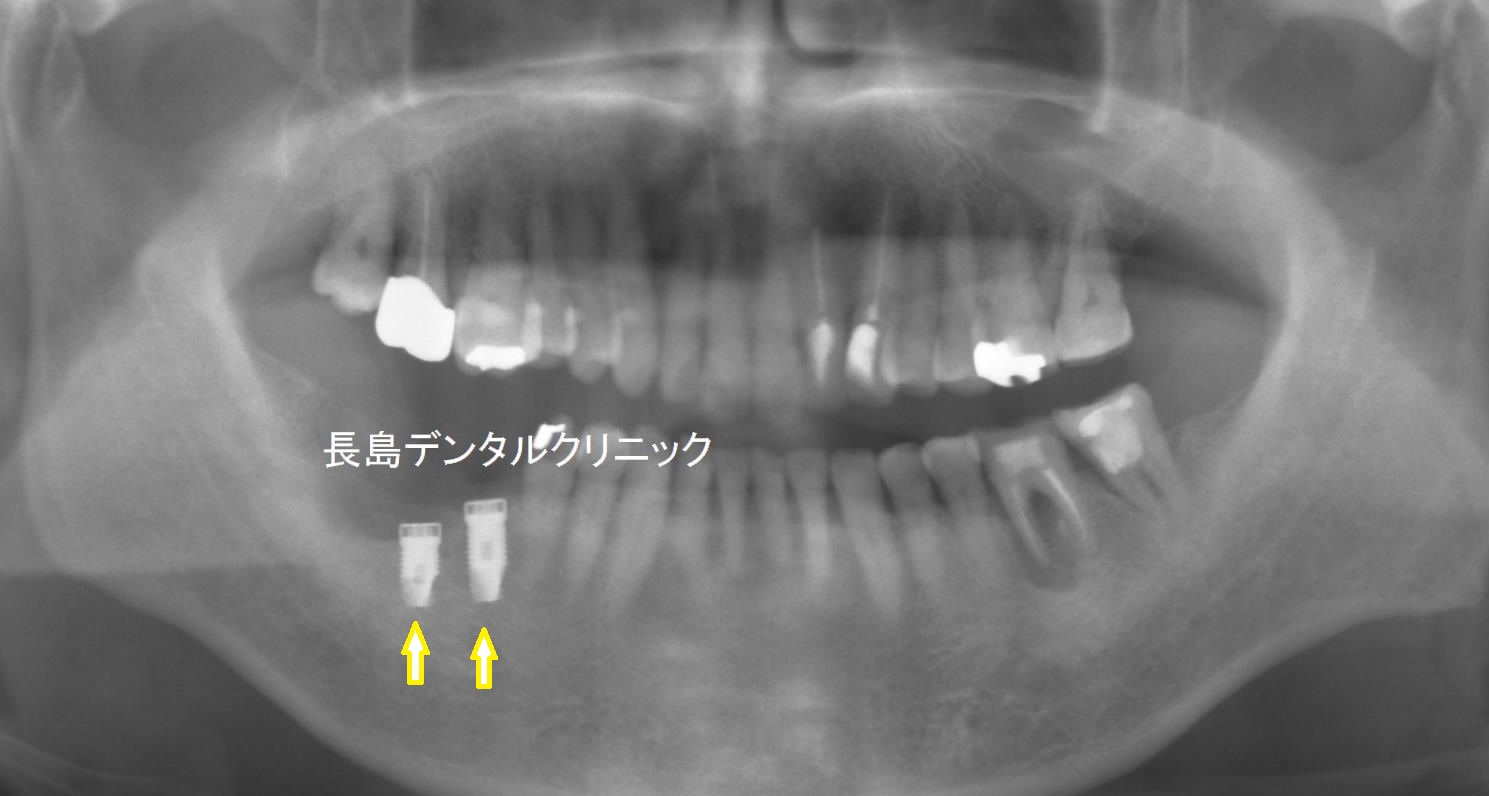

2、インプラント埋入

2本抜歯を行いインプラントを埋入します。

患者様は噛む力が強いため

幅の太いインプラントを使用しました。

インプラントを埋入し3か月で

インプラントは骨としっかり結合したこと

確認後 上部構造の製作に移ります。